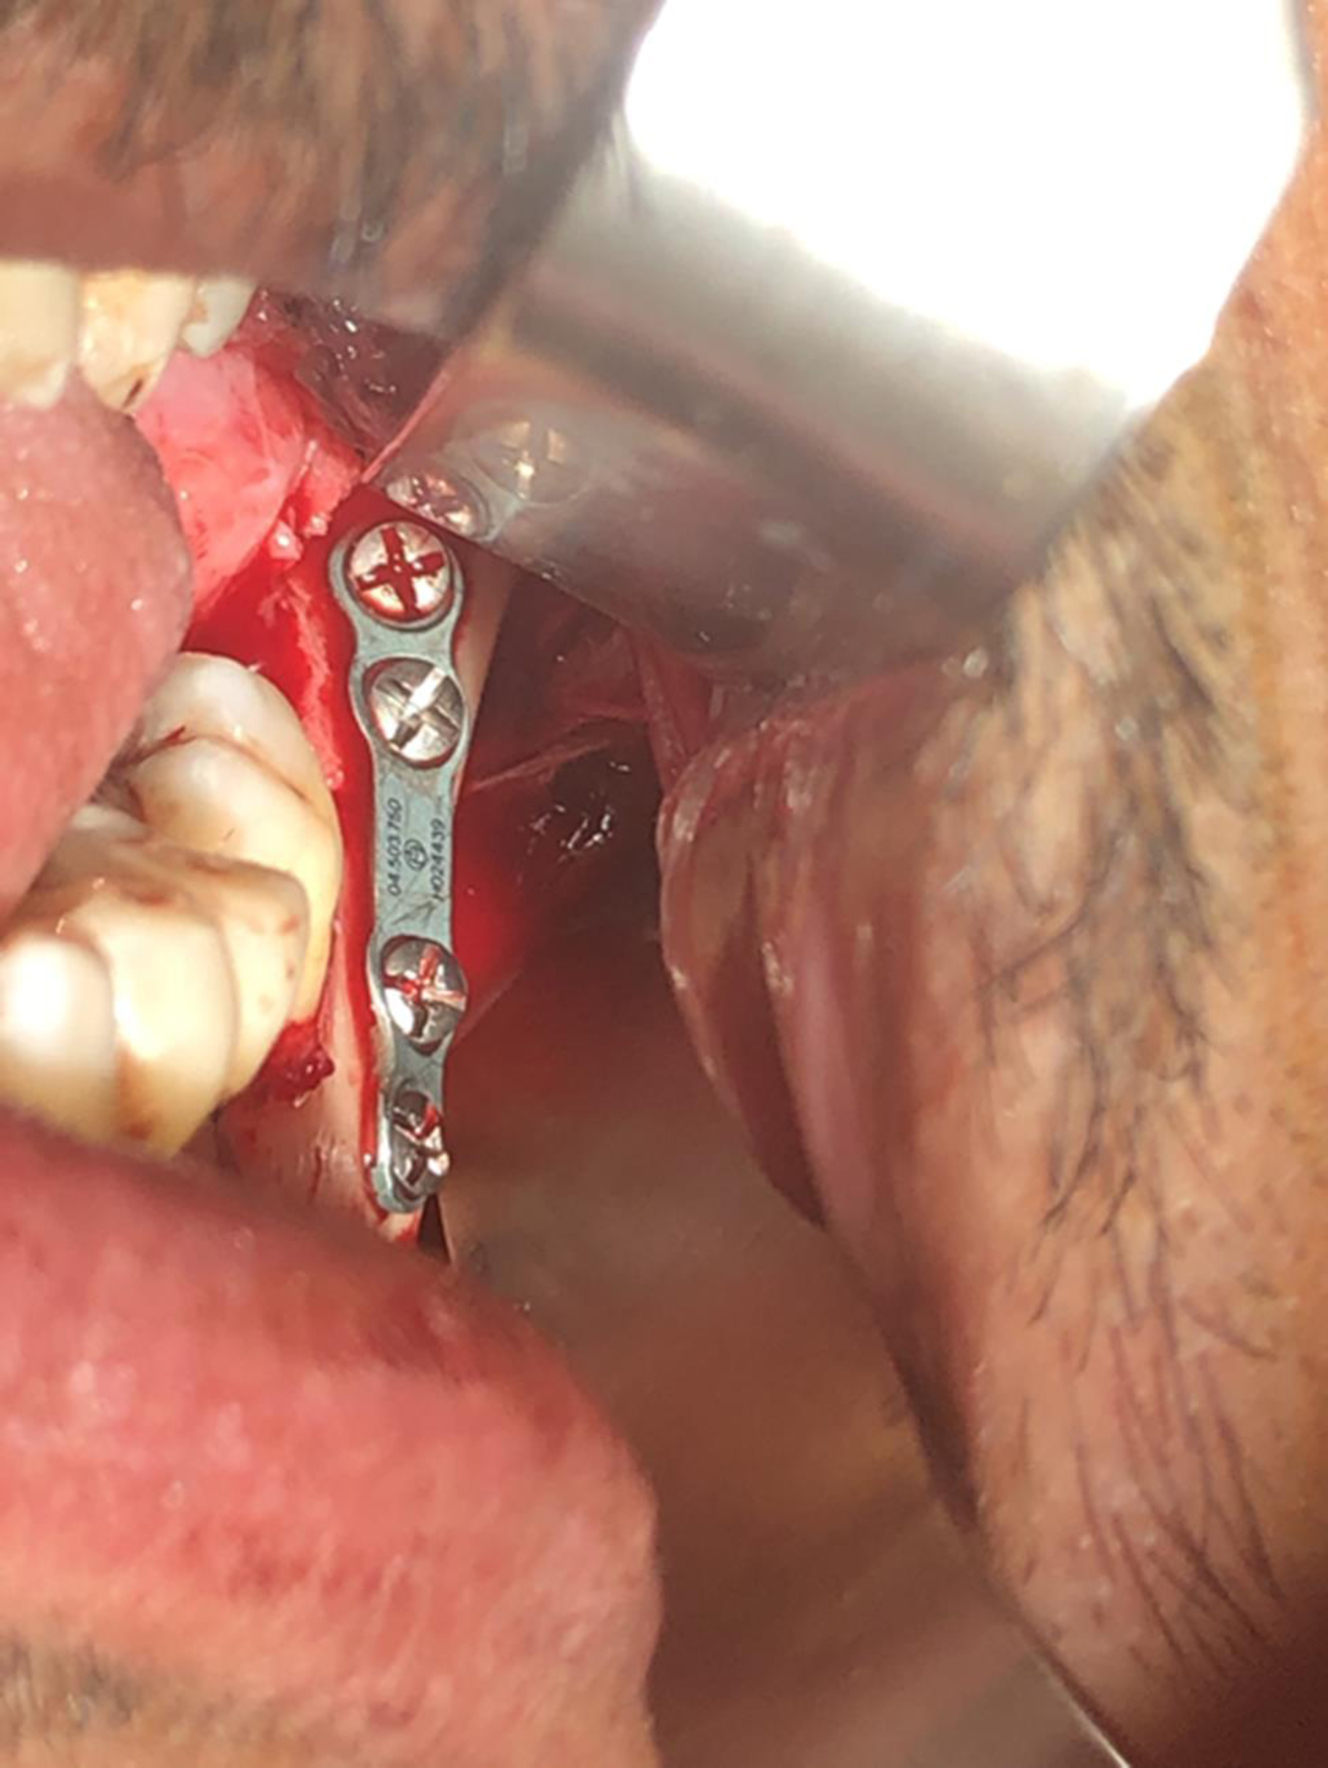

When approaching a MAF, several important factors must be considered. A key determination is the presence or absence of other mandibular fractures. The presence of other fractures may determine the order or technique of the approach. For instance, if there is a nondisplaced contralateral condyle fracture, this circumstance portends the need for guiding elastics, and the use of Erich arch bars will likely be the first step in fracture repair. Angle fractures are usually “retro-occlusal” in that they occur behind the articulated dentition. Therefore, if other fractures are present in the dentate segment of the mandible, it is these “occlusal” fractures that strategically are approached first. Fractures of the mandibular angle are often approached transorally through an incision proximate to the retromolar trigone or through a gingival incision that is described for third molar extraction. In the case of an isolated angle fracture, the fracture is typically completely exposed, and reduction is attempted before placing the patient into maxillomandibular fixation. Yet, maxillomandibular fixation would typically be a prerequisite to plating of the fracture as MMF is typically beneficial to achieving optimal fragment reduction. Temporary MMF techniques include the use of intermaxillary fixation (IMF) titanium screws, the use of Ivy loops, or the use of Ernst ligatures along with several other methodologies including a type of zip tie or embrasure wires. The instrumentation for the transoral approach to the angle uses transbuccal trocars for the plate and screw placement. It is beneficial to use threaded locking plates in the repair because the threaded locking plates can be secured directly to the transbuccal trocar to allow control of the plate while the repair is being secured and for drilling screw holes ( Fig. 1 ). Headlights and surgical magnification using loupes or endoscopes can improve visualization during the repair.

Although not original to Champy’s description, monocortical miniplate placement on the lateral boarder of the angle in a superior position has been shown to have the lowest complication rate in the literature ( Fig. 6 ). Specifically, plate dehiscence has an odds ratio five times lower if the plate is placed on the lateral mandibular surface rather than on the external oblique ridge. The success of this technique may have to do with having more facile operative access through the transoral approach for this position of plate placement. The Champy technique is based on obviating tensile force, and placement of a plate on the lateral boarder can accomplish that task efficiently.

The lateral inferior boarder also can be used for load-bearing rigid fixation using bicortical screws and thick plates designed to bear the complete load of mandibular function. Three holes on each side of the fracture would be considered the minimum optimal engineering necessary to accomplish safe immediate function. The placement of such thick and large hardware in this position is often accomplished through an external skin incision to allow optimal exposure for plate placement and plate contouring. The choice of this technique is made when fractures are comminuted, when the mandible is edentulous and atrophic with loss of alveolar bone stock, or when there is tooth loss which reduces contact surface area. Load-bearing approaches are also preferential in circumstances where infection is present ( Fig. 7 ).